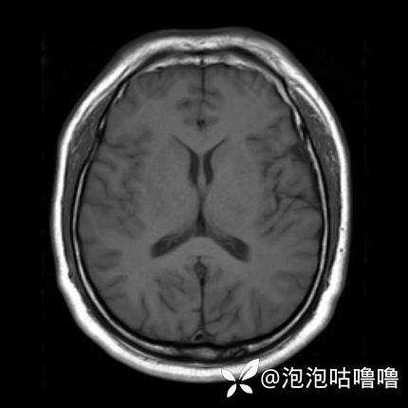

头颅MRI(磁共振成像)

MRI是诊断早期脑梗的“金标准”。

- 超早期诊断: 对于发病后仅一两个小时的脑梗,MRI上的DWI(弥散加权成像)序列就能非常敏感地显示出缺血坏死的区域,比CT早得多。

- 敏感性高: 能发现非常小的、CT难以显示的梗死灶。

- 鉴别诊断: 能更好地区分脑梗和其他疾病,如脑肿瘤、脑炎等。